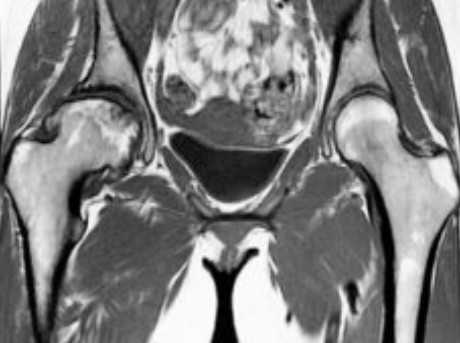

МРТ костей таза показывает множественные очаги, что говорит о метастатическом поражении

Магнитно-резонансное сканирование с контрастированием улучшает возможности визуализации. Исследование с усилением проводят для диагностики опухолевого процесса, включая обнаружение метастазов в костях таза, раннего выявления рецидива новообразования после лечения, уточнения степени выраженности воспалительного процесса, деструкции и пр. Контраст на основе гадолиния обладает высоким профилем безопасности и не требует предварительной оценки функции почек. Побочные эффекты на введение парамагнетика регистрируют крайне редко. В 99,9 % случаев исследование проходит без осложнений. Противопоказания к контрастированию: